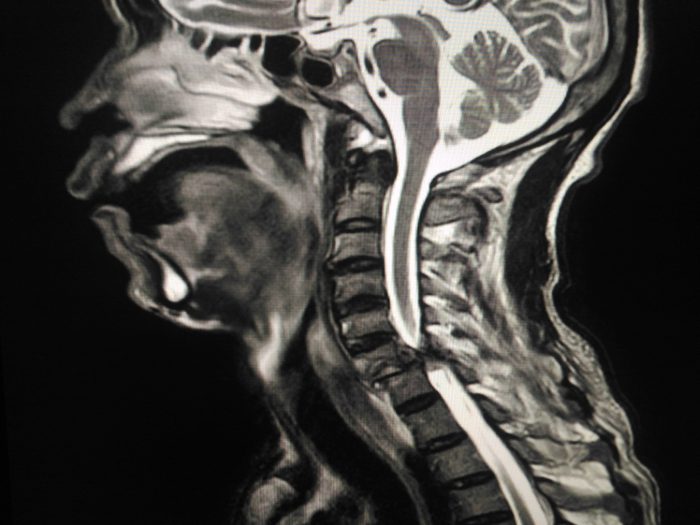

After five years: Stroke risk is significantly lower

The long-term effects of better heart health and lower blood pressure grants you another significant benefit: Lower stroke risk. Compared to nonsmokers, e-cigarette users have a 71% higher risk of stroke, according to research presented at the 2019 International Stroke Conference. Quitting can lower that risk almost immediately, but the risks continue to fall with each passing calendar month.

A decade later: Lower cancer risks

A 2017 study published in Scientific Reports suggests e-cigarettes and vaping may lead to DNA changes and genetic mutations that can increase the risk of cancer. So the longer you avoid e-cigarettes, the healthier your body will be. “After a decade, lung cancer risk is reduced by 50%, as well as the risk of pancreatic, mouth, and throat cancer,” Dr. Djordjevic says. “After 15 years, your risk of developing coronary heart disease becomes the same as a nonsmoker’s. The same goes for the risk of developing pancreatic cancer.”